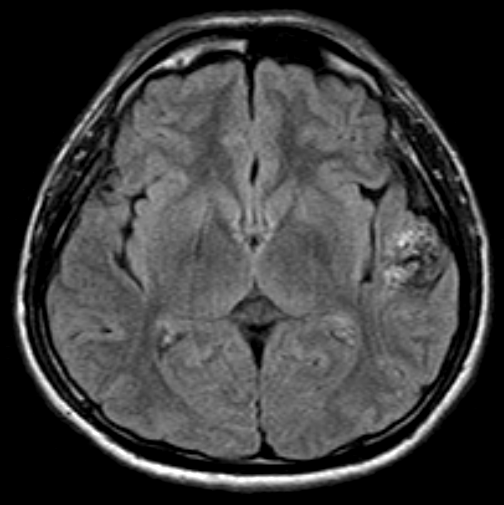

Khoa Chẩn đoán hình ảnh đã tiến hành chụp MRI sọ não với các xung MRA, MRV, dựng hình mạch máu não. Kết quả cho thấy, Bệnh nhân bị dị dạng mạch máu não (AVM) vùng thái dương bên trái có nguồn cung cấp máu từ động mạch não giữa cùng bên (bên trái), tĩnh mạch hồi lưu về xoang tĩnh mạch bên (bên trái).

Hình ảnh tổn thương

FLAIR